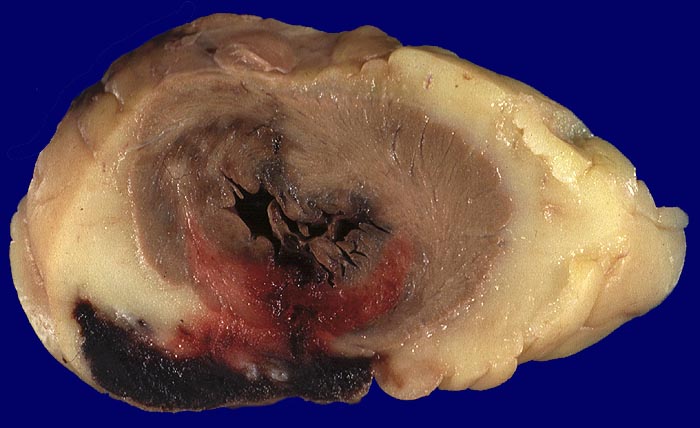

AP/ Akuter Myokardinfarkt

Akuter Myokardinfarkt

Makroskopie

Pathologischer Befund